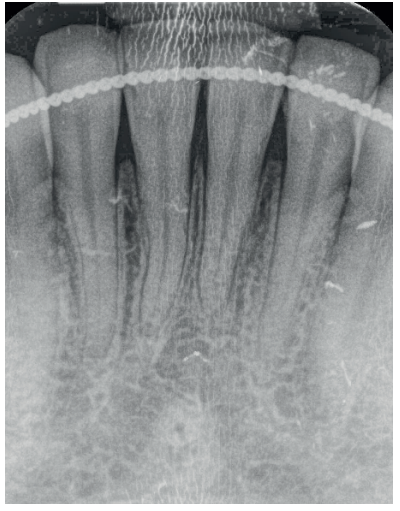

La fluorosis dental es una condición irreversible originada durante el desarrollo dental que genera pigmentaciones intrínsecas, alteraciones en el esmalte manifestadas a manera de manchas blancas, amarillas o marrones, que perjudican la estética y repercuten en el desenvolvimiento social. El presente reporte de caso clínico describe la combinación de los procedimientos de microabrasión y blanqueamiento dental, como alternativas en la eliminación de pigmentaciones dentales. Después del diagnóstico de la patología, verificación de ausencia de lesiones pulpares y caries, una explicación minuciosa a la paciente y obtención del consentimiento informado, se realizó limpieza de las superficies dentales y, bajo aislamiento absoluto, se procedió a realizar la técnica de microabrasión mediante ácido clorhídrico al 6,6% siguiendo las instrucciones del fabricante. Concluido el procedimiento y, observando que era posible mejorar aún más la estética, se decidió ejecutar el procedimiento de blanqueamiento dental, a base de peróxido de hidrógeno al 40% en el consultorio, seguido por peróxido de carbamida al 10% aplicado en el domicilio. Al finalizar el tratamiento se observó uniformidad en el color dental, conjugados con una evidente mejora en la calidad de vida y relación social de la paciente.